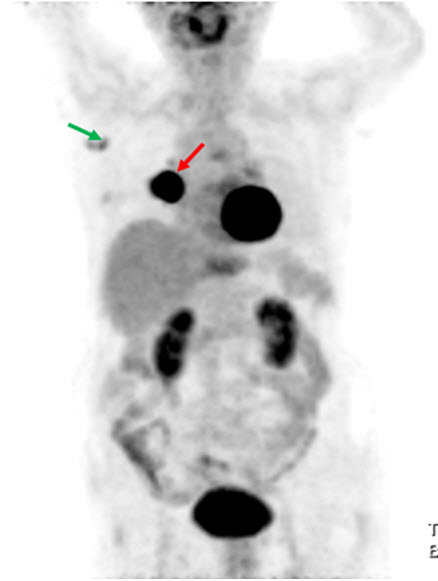

Hình 7. Bệnh nhân Nguyễn Th. M. T., nữ, 51 tuổi, chẩn đoán: Ung thư vú trái đã phẫu thuật. Bệnh nhân được chụp PET/CT mô phỏng lập kế hoạch xạ trị hậu phẫu. Trên hình PET/CT mô phỏng thấy rõ hạch nách trái và hạch vú trong. (Nguồn: Mai Trọng Khoa – Trung tâm Y học hạt nhân và ung bướu – BV Bạch Mai)